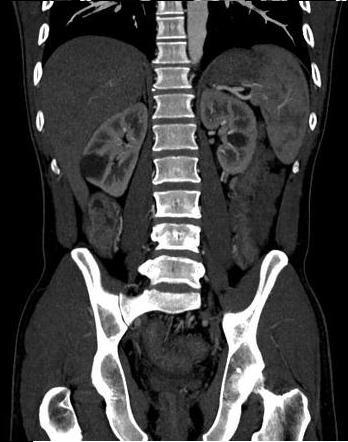

. Image TDM du maladie de

Crohn dans phase aigue est image

de epaissisement parietale avec oedeme sous muqueuse

discontinunite et signe de peigne " comb sign ". En phase

chronique cicatricielle ,aspect radiologique est image

epaissisement homogene de la paroi avec infiltration graisseuse parietale ou mesenterique

en forme de image de cible " fat halo sign". Stenose ,fistule et

abces sont des images de sa complication .

Stenose epaisissement colique

gauche et sigmoidienne avec halo graisseux d'une

maladie de Crohn . Image de hypervascularisation et

infiltration de la graisse sous-muqueuse , aspect en

peigne " Comb sign ". Image TDM en coupe coronale |

|

Image de

hypervascularisation " Comb sign " et epaissisement

de la paroi du ileon se voyait si nette sur les

coupe TDM axiale |